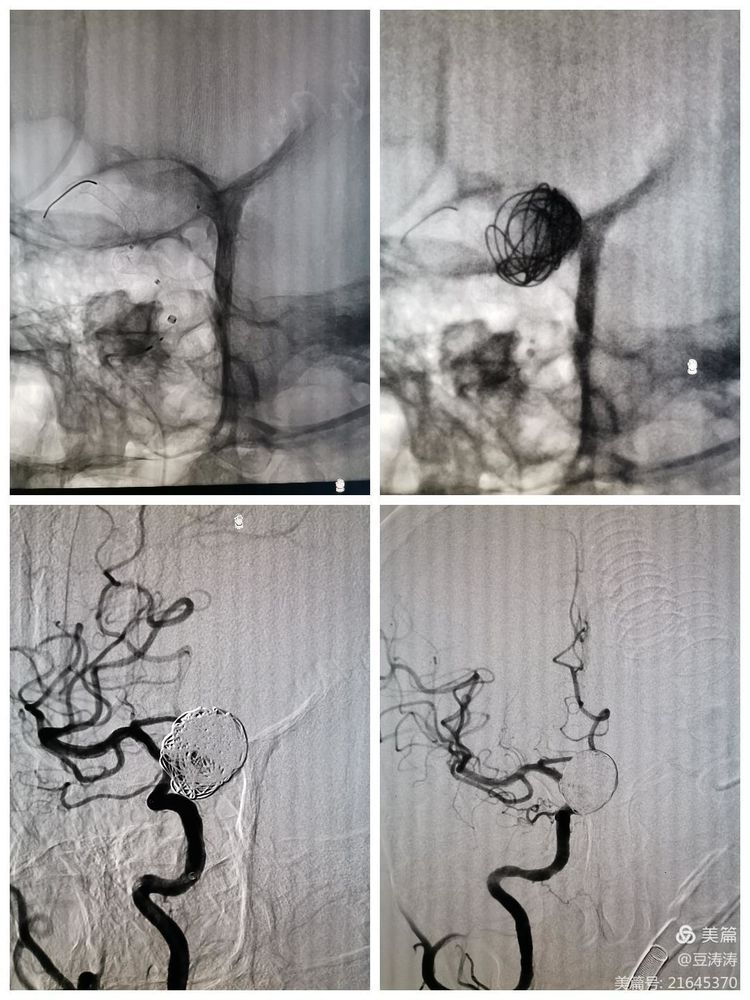

正侧位及工作位造影。

FD释放,弹簧圈稀疏栓塞动脉瘤。造影,载瘤动脉通畅,动脉瘤不显影。

此病例是九院神经外科团队首次采用FD治疗颅内复杂动脉瘤并取得良好效果。该技术使得颅内动脉瘤治疗方式,发生了"从堵到疏"改变。使得颅内动脉瘤的治疗方式更加简单,提高了动脉瘤的治愈率,特别是对颅内复杂动脉瘤的治疗,填补了我院的空白。